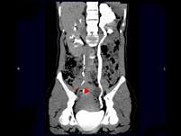

- 多项选择题女,42岁, 左侧腰背部胀痛不适1年余,5年前行左侧卵巢囊肿切除术, CT检查如图所示,下列说法正确的是 ( )

A、左侧附件区可见一囊性肿物,压迫输尿管下段

B、左侧输尿管下端狭窄

C、左侧肾盂肾盏扩张积水

D、左侧输尿管中上段扩张

E、考虑为左侧卵巢囊肿术后复发压迫并粘连输尿管致其狭窄